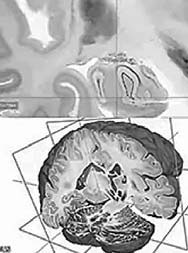

Bilingual: Scientists have created a high-resolution 3-D atlas of the human brain. The digital three-dimensional model called "BigBrain" was made using thousands of sections from the brain of a 65-year-old woman. The resolution is finer than a human hair, so it can reveal clusters of the brain.